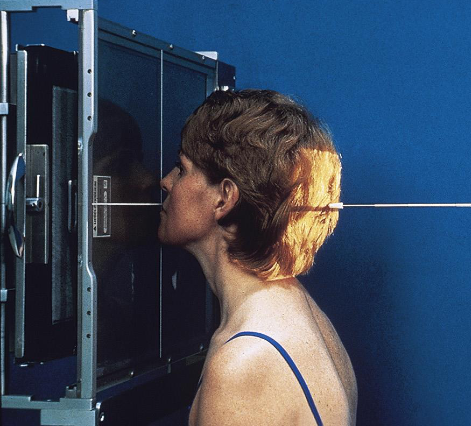

PA mandibular rami

patient position:

prone or upright

part position:

forehead and nose resting on IR

OML perpendicular to IR

MSP perpendicular to Ir

respiration suspended

CR:

perpendicular, exits acanthion

collimation:

1 inch beytond the lateral sides, above the TMJs, and below the chin